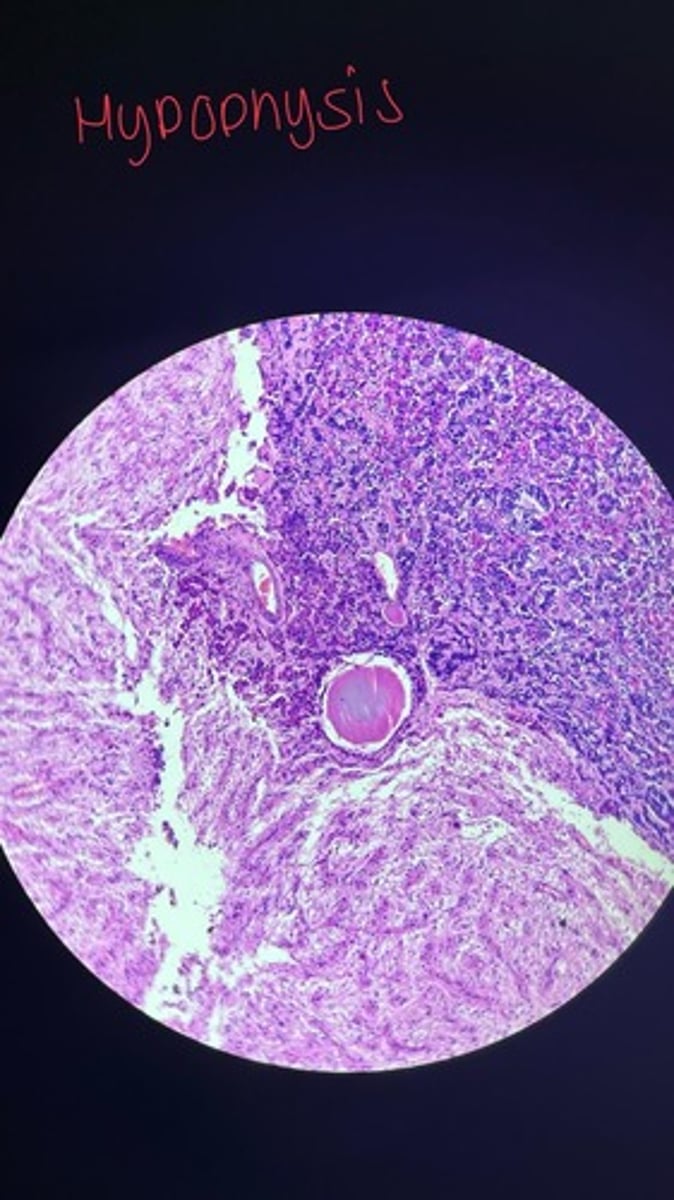

Hypophysis cerebri HE

Hypophysis cerebri HE

Hypophysis cerebri HE

Hypophysis Cerebri HE

Hypophysis cerebrospinal HE

Hypophysis cerebri HE